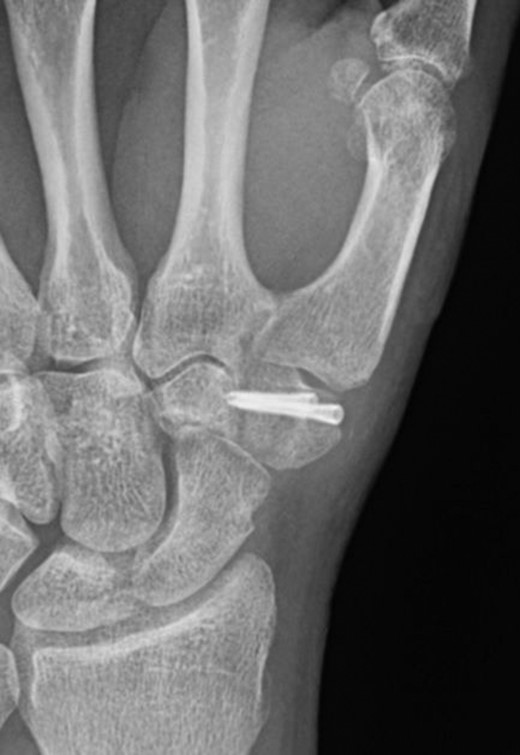

A 49-year-old man fell from his mountain bike at speed and presented to his local secondary care hospital with an injury to the base of his left thumb. There was pain and swelling at the base of the thumb with painful restriction of movements. Initial radiographs were deemed to be normal and he was treated as a soft tissue injury with a period of immobilization followed by physiotherapy. The patient was referred to us four months later as the pain and weakness were persisting. A thorough retrospective perusal of his history and imaging to date was carried out. A review of his initial plain radiographs (Fig. 1) and MRI scans indicated a fracture of the left trapezium and a CT scan was obtained to further characterize the anatomy of the fracture.